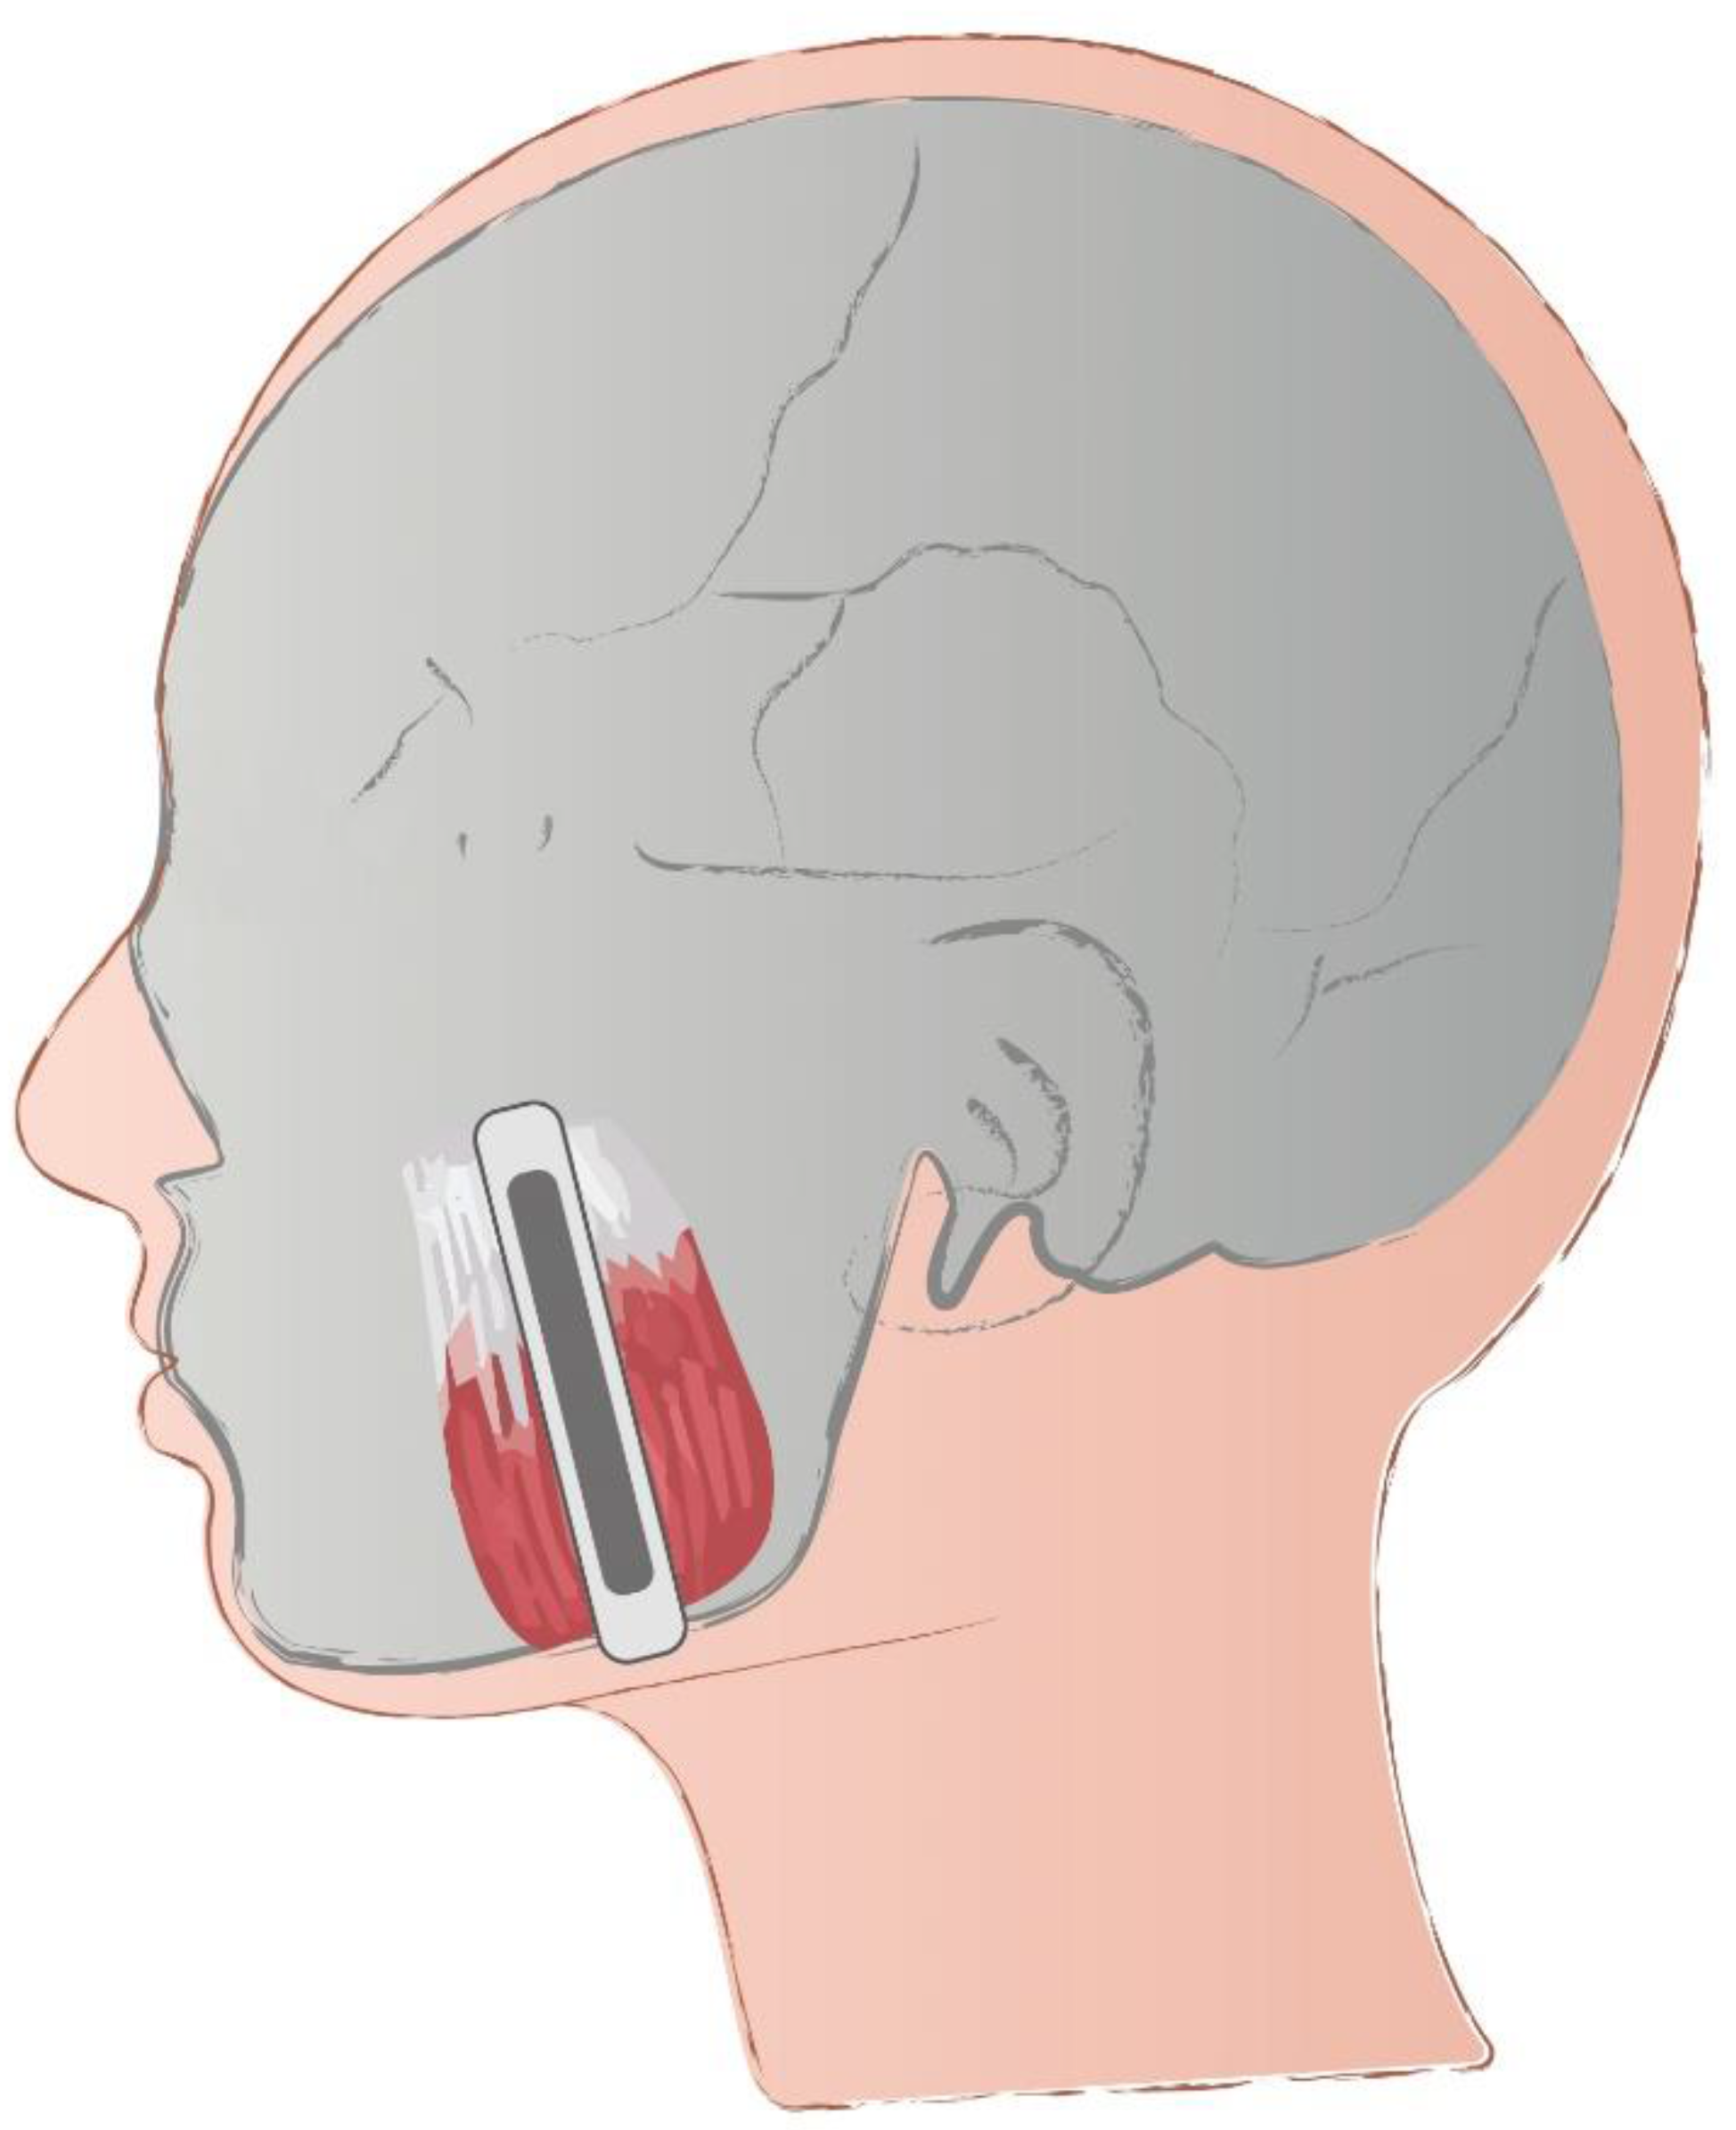

Determination of Reference Values of the Masseter Muscle Stiffness in Healthy Adults Using Shear Wave Elastography

- Olchowy, C.; Więckiewicz, M.; Sconfienza, L.M.; Łasecki, M.; Seweryn, P.; Smardz, J.; Hnitecka, S.; Dominiak, M.; Olchowy, A. Potential of Using Shear Wave Elastography in the Clinical Evaluation and Monitoring of Changes in Masseter Muscle Stiffness. Pain Res. Manag. 2020, 2020, 4184268. [Google Scholar] [CrossRef] [PubMed]

- Olchowy, C.; Olchowy, A.; Hadzik, J.; Dąbrowski, P.; Mierzwa, D. Dentists can provide reliable shear wave elastography measurements of the stiffness of masseter muscles: A possible scenario for a faster diagnostic process. Adv. Clin. Exp. Med. 2021, 30, 575–580. [Google Scholar] [CrossRef]

- Olchowy, A.; Wieckiewicz, M.; Winocur, E.; Dominiak, M.; Dekkers, I.; Łasecki, M.; Olchowy, C. Great potential of ultrasound elastography for the assessment of the masseter muscle in patients with temporomandibular disorders. A systematic review. Dentomaxillofac. Radiol. 2020, 49, 20200024. [Google Scholar] [CrossRef] [PubMed]